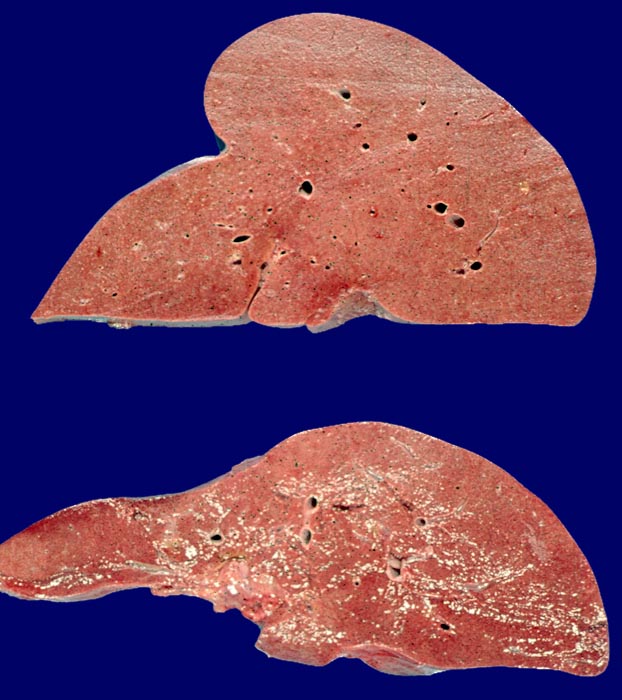

Amyloidose der Leber (oben), Normalbefund (unten)

Die Amyloidoseleber ist vergrössert. Die Schnittfläche erscheint sehr fest, das Gewebe sehr kompakt. Unten im Bild normale Vergleichsleber.